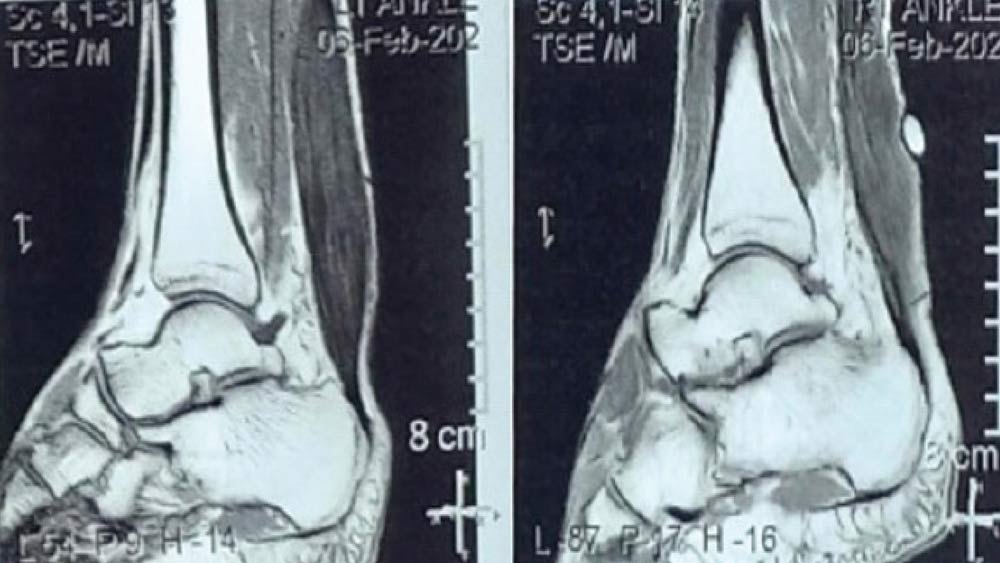

A 42-year-old male presented with a 6-year history of asymptomatic swelling in the distal aspect of both legs. On examination, firm, non-tender, non-reducible, and non-mobile masses were observed without signs of inflammation, and the patient maintained full ankle joint mobility. Magnetic resonance imaging findings revealed diffusely bulky Achilles tendons with specific imaging characteristics consistent with xanthomatosis (Figure). Further evaluation of the lipid profile confirmed hypercholesterolemia and hyperlipidemia. Given the absence of pain or movement restrictions, the patient was managed conservatively with monitoring and treatment for his lipid abnormalities.